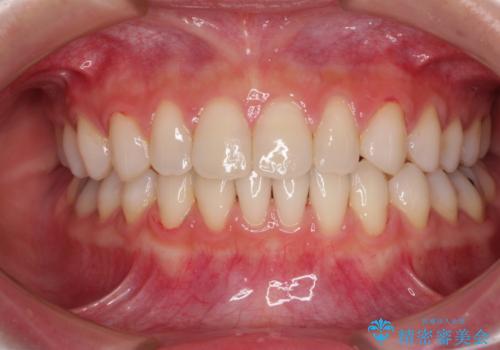

歯肉の腫れた前歯 部分矯正と歯周外科後の審美治療

- 前歯の歯茎に違和感を感じるとのことで来院された患者様です。

左上中央の歯は根の深くまで割れており、抜歯が必要との診断となりました。

それ以外の3歯も歯肉深いところまでクラウンが装着されていたため、歯周外科(歯肉弁根尖側移動術)を行った後にオールセラミッククラウンにて補綴することとしました。

また、下の前歯が隠れてしまうほど上の前歯が下に降りていることを気にされていたため、部分矯正により前歯の位置を事前に改善することとしました。